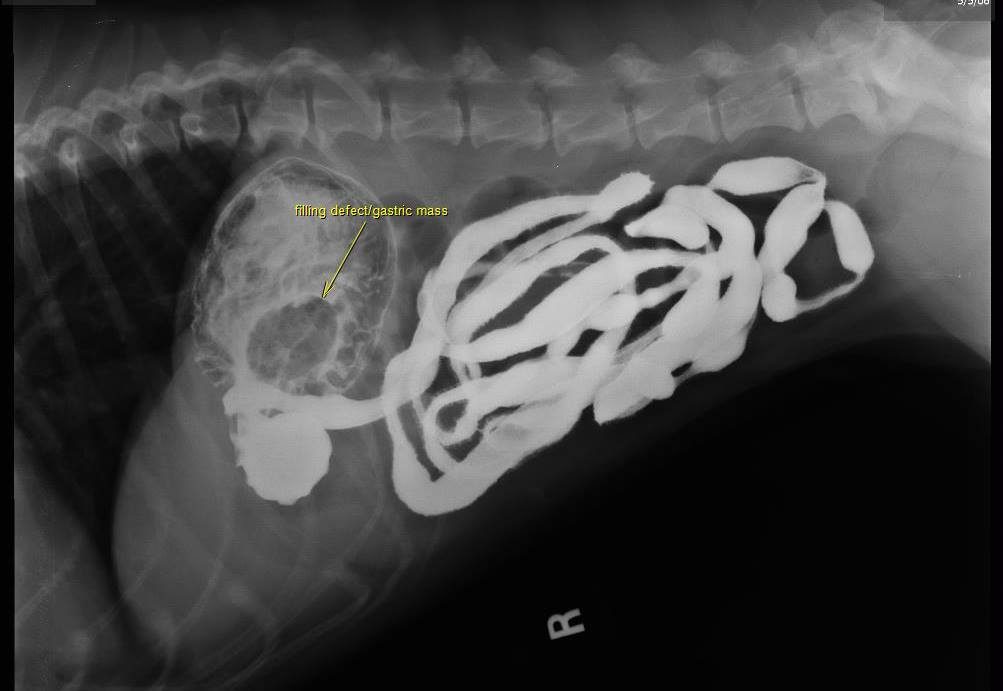

This is a case of a 10-year-old female spayed Boxer who has been anorexic intermittently for several weeks. Over the last week, the owner has had to syringe feed. Prior to onset, P was treated for cystitis, which resolved. Treatment for gastritis, including sucralfate, famotidine, and triamcinolone was only effective for a few days at a time. Chemistries on April 25 showed a slight elevation of lipase. CBC had very mild lymphopenia. Previous surveys' results were unremarkable for GI. Only 2 instances of vomiting have occurred during this time.

On the survey study you can see a soft tissue opacity in the stomach. However, be careful not to overinterpret this on a non-contrast image. Fluid in the stomach can often have this appearance and you can get a false impression of gastric wall thickening due to the air/fluid interface. However post adminstration of barium, we can now see a gastric mass causing a filling defect in the gastric wall on numerous images, and this confirms that what we saw on the survey images was a real finding. The contrast will surround the mass causing it to appear radiolucent and allowing us to define the margins. Primary differentials, particularly in this age and breed, would be neoplasia (lymphoma, adenocarcinomva).

Would you see this on ultrasound? Potentially, but it depends on your skill level in sonography, how much air is in the stomach, where in the stomach it is located, etc. So if you do not have access to ultrasound (or even if you do) or if you were unable to get a good view of the gastric wall this is a great study to do! Thank you to Dr. Greg Emmert (one of my vet school classmates!) and McGee Street Animal Hospital for this fascinating case!